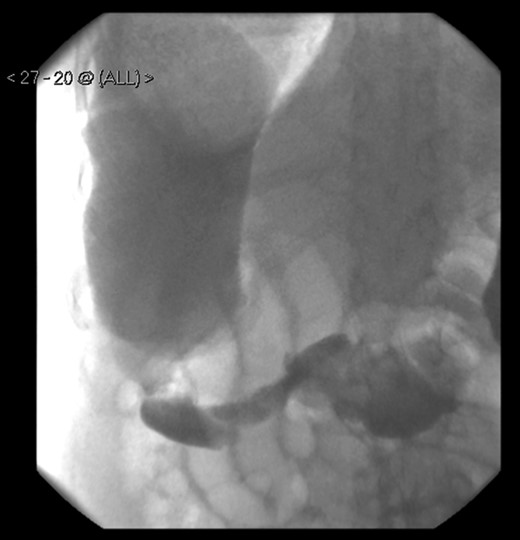

A 58-year-old female with a past medical history of a large intrathoracic hiatus hernia presented to her general practitioner and was subsequently referred to our surgical department with symptoms of sudden onset severe epigastric pain associated with vomiting and abdominal distension. Her abdomen was generally tender, maximally in the epigastric region, although she was not peritonitic. The admission erect chest radiograph showed a large hiatus hernia and an elevated right hemidiaphragm with a large loop of distended bowel (Fig. 1). Subsequent computed tomography (CT) scan demonstrated an almost completely intrathoracic stomach with a degree of volvulus, and the liver medially displaced by a loop of large bowel felt to be caecum (Fig. 2). Since the patient remained otherwise well, bidirectional endoscopy was performed, and given that a volvulus point could not be identified and the ileocaecal junction was not identified, contrast studies were requested (Figs 3–5) which demonstrated an incomplete obstruction caused by a volved caecum rotated anteriorly and cephalad.

A large bowel contrast study showing the flow of contrast from the collapsed transverse colon into the dilated, upwardly displaced caecum.